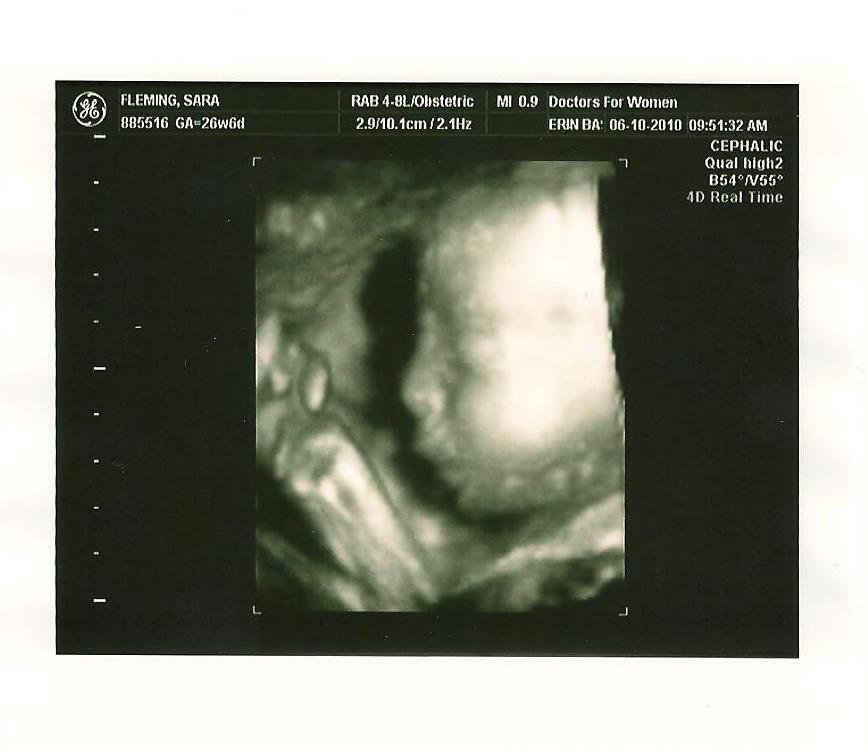

Last Thursday was the 4D Ultrasound!! I know you are ready to see those pictures, so here we go:

"Hi there, I'm baby boy Fleming! Aren't I cute as can be? I weigh about 2 lbs. here!"

"Hi there, I'm baby boy Fleming! Aren't I cute as can be? I weigh about 2 lbs. here!"  "Everybody says I look just like my Daddy. I have his nose and profile. But, I also have Mommy's cheeks and rounder face!"